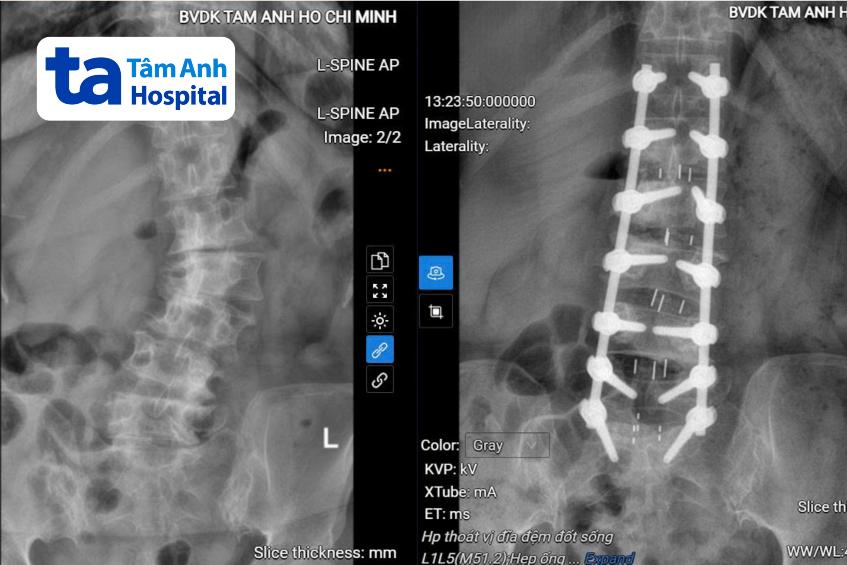

ThS.BS Đàng Quốc Duận, khoa Phẫu thuật Cột sống, Bệnh viện Đa khoa Tâm Anh TP HCM, cho biết người bệnh bị tổn thương kéo dài từ đốt sống L1 đến S1 với các vấn đề như vẹo cột sống do thoái hóa, hẹp ống sống nặng, thoát vị đĩa đệm chèn ép thần kinh.

Đầu tiên, bác sĩ thực hiện giải ép ống sống bằng cách loại bỏ các cấu trúc gây chèn ép và mở rộng ống sống, từ đó tạo khoảng không gian để giải phóng tủy và các rễ thần kinh. Tiếp theo, các phần đĩa đệm thoát vị, gai xương… được loại bỏ và tiến hành thay đĩa đệm để hàn khớp liên thân đốt sống đảm độ vững của cột sống. Cuối cùng, là bắt vít cố định và nắn chỉnh lại cột sống của người bệnh.

Trong quá trình phẫu thuật, hệ thống C-arm đã được sử dụng để hỗ trợ bác sĩ định vị chính xác vị trí bắt vít, giảm nguy cơ tổn thương thần kinh, rút ngắn thời gian phẫu thuật. Nhờ đó, giảm nguy cơ mất máu và hạn chế xâm lấn, người bệnh phục hồi nhanh hơn. Ca phẫu thuật kéo dài 5 giờ, 14 vít đã được sử dụng.